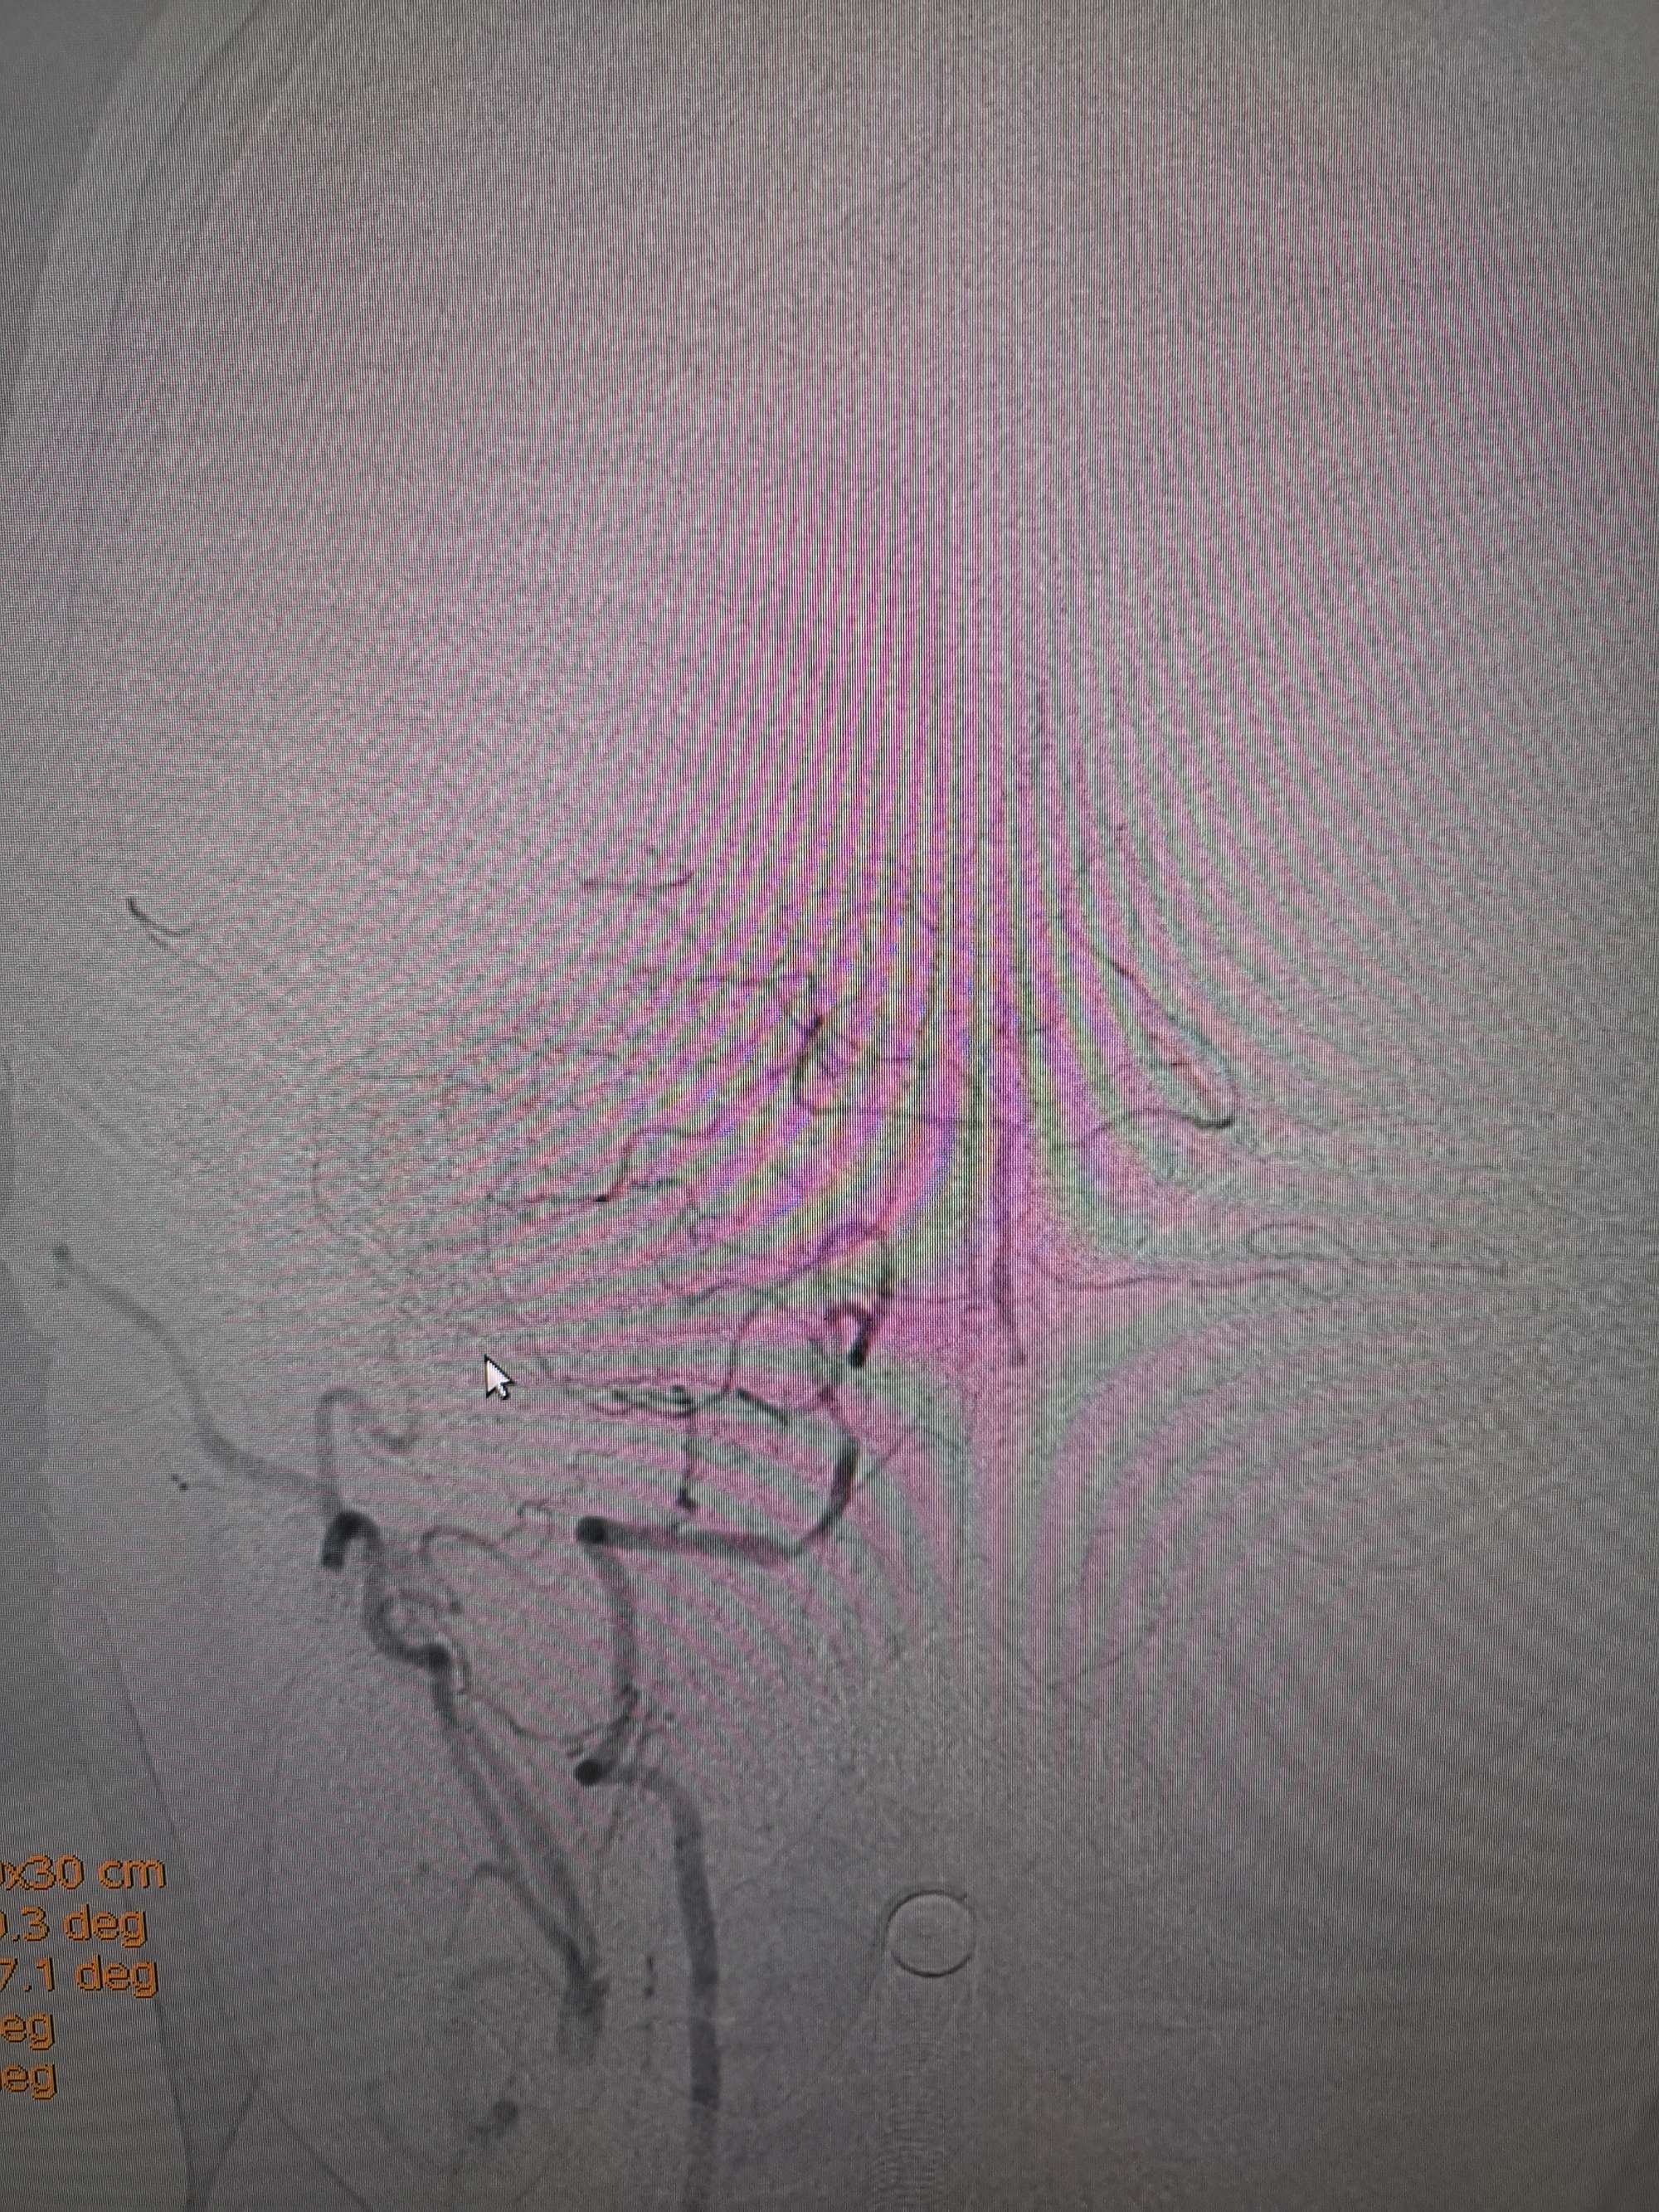

手术过程

在微导管支撑下先将微导丝和微导管穿过闭塞段,微导管超选造影证实位于基底动脉真腔后更换300cm外周交换导丝,撤出微导管后按从小到大,从远到近的原则行球囊扩张,本例手术选择了1.5✖️15、2.0✖️20、2.5✖️20球囊进行扩张,扩张满意后植入Enterprise支架,手术结束。